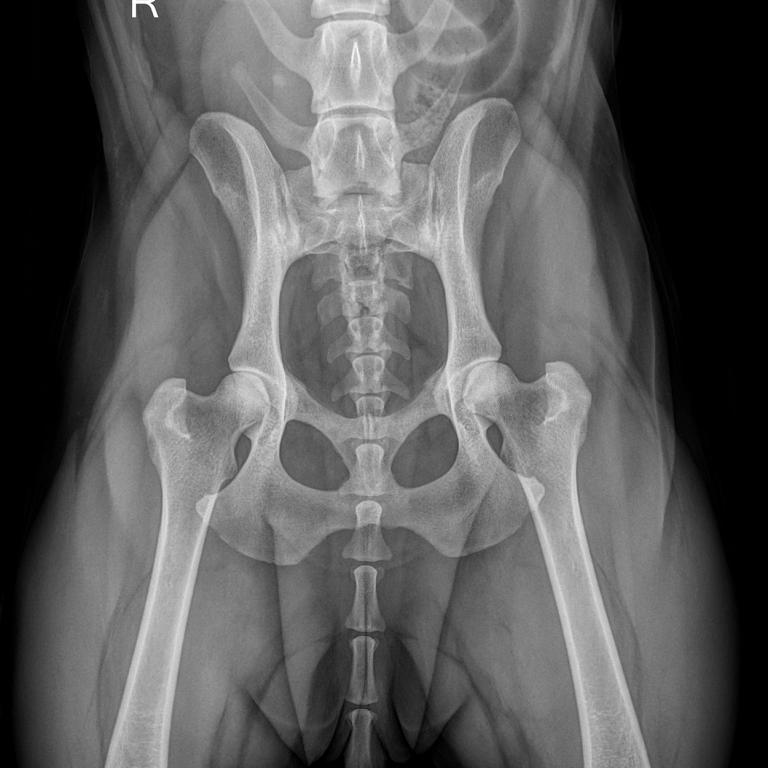

Unsere leistungsfähige Röntgenanlage ermöglicht die Anfertigung qualitativ hochwertiger Aufnahmen von der Katze bis zum Bernhardiner. Röntgenuntersuchungen sind vor allem bei orthopädischen Erkrankungen das Diagnostikum der Wahl, aber auch bei Herz- und Lungenerkrankungen, zur Darstellung von röntgendichten Fremdkörpern und zur Erkennung von Lungentumoren und -metastasen eignet sich die Röntgenuntersuchung hervorragend. Natürlich führen wir auch Zuchttauglichkeitsuntersuchung auf HD, ED und OCD durch.